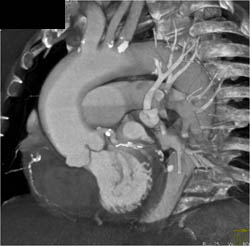

Dilated Ascending Aorta